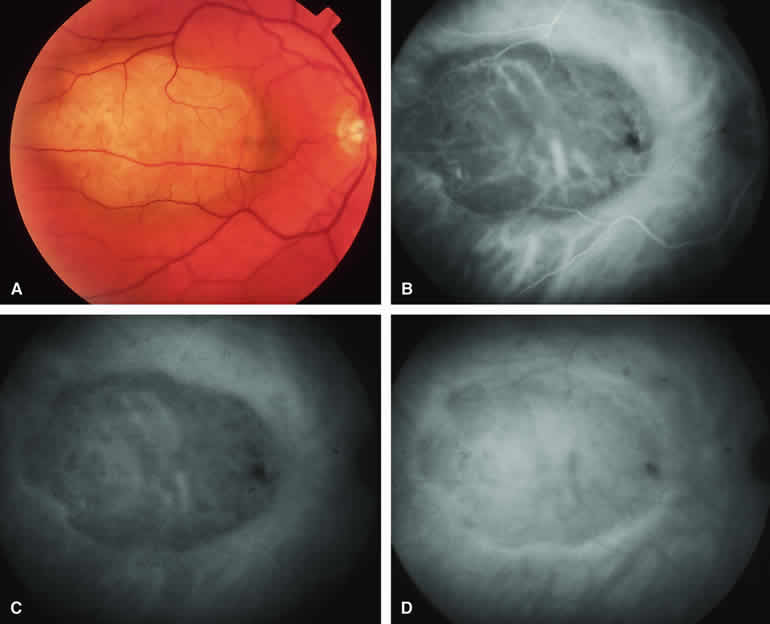

Amelanotic Choroidal Nevus

Approximately 10% to 15% of choroidal nevi are largely or completely amelanotic clinically. Fluorescein and ICG angiography of an amelanotic choroidal nevus (see Fig. 3) tend to show less prominent hypofluorescence of the lesion than they do with darkly melanotic nevi. Because of the lack of intracellular melanin pigment within the nevus cells, some large-caliber choroidal blood vessels running through the nevus may be visible in the region of the mass (see Fig. 3B and C). These choroidal blood vessels are better defined by ICG angiography than by fluorescein angiography. Amelanotic choroidal nevi often appear mildly hyperfluorescent in late-phase frames (see Fig. 3D).